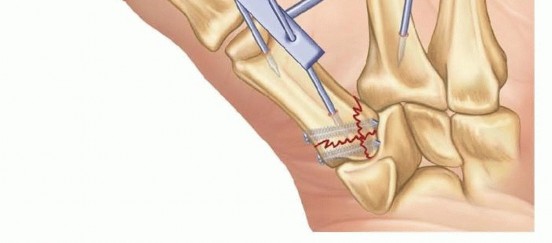

Fixation Strategies for Rolando and Comminuted Patterns

Rolando fractures present a significantly higher degree of complexity. The classical Y or T pattern often precludes simple lag screw fixation. In these instances, mini-fragment plating is the gold standard. T-plates or specialized condylar plates are contoured to fit the complex geometry of the metacarpal base. The articular fragments are first reduced and provisionally pinned, essentially converting the complex intra-articular fracture into a simpler two-part extra-articular fracture. The plate is then applied to buttress the articular fragments and bridge the metaphyseal comminution to the diaphysis.

Image

In cases of severe, non-reconstructable articular comminution where internal fixation is impossible, joint-spanning external fixation combined with limited internal fixation (K-wires) is utilized. The external fixator relies on the principle of ligamentotaxis to restore length and align the articular fragments. Pins are placed in the trapezium (or radius) and the thumb metacarpal shaft, distracting the joint to allow for secondary bone healing while preventing collapse.